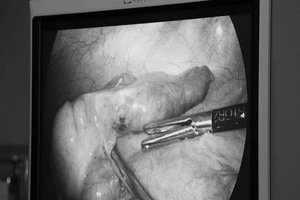

Bác sĩ luân phiên công tác và chuyện mổ ruột thừa ở đặc khu Côn Đảo

Cứu sống 2 bệnh nhân viêm ruột thừa kết hợp nhồi máu cơ tim cấp

Vụ 'viêm ruột thừa, cắt buồng trứng': Rất dễ chẩn đoán nhầm!

Bình Dương: Bệnh viện lên tiếng vụ đau ruột thừa nhưng cắt buồng trứng

Viêm ruột thừa do nuốt xương cá nhiều năm không hay biết

Thai phụ suýt chết vì viêm ruột thừa nhưng tưởng đau bụng đẻ

Dấu hiệu viêm ruột thừa

Tử vong vì bị cắt túi mật khi mổ ruột thừa